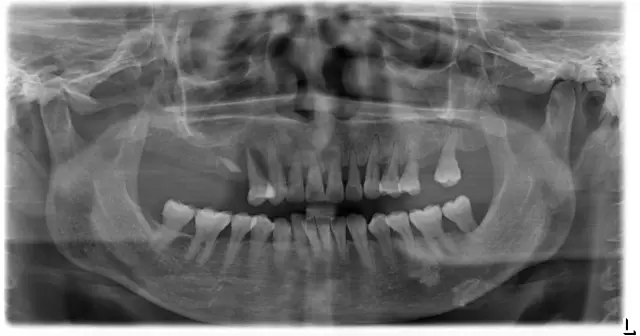

比苏阿姨还年轻的一位美奥种植牙患者,缺牙严重,影响吃饭咀嚼,间接影响了消化和肠胃。

▲种植前